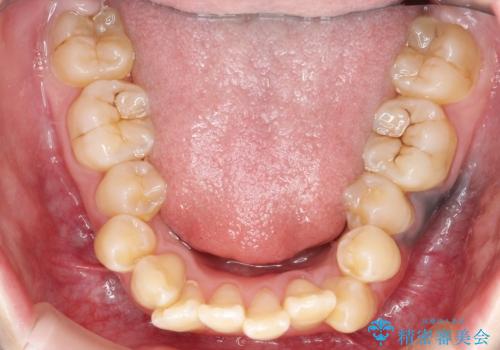

重度のガタガタ ワイヤーによる抜歯矯正

- 出っ歯と全体的ながたつきを主訴に来院されました。

上下の歯に重度のガタガタがあり、前歯が下の歯と咬んでいない状態でした。

審美装置を用いた、抜歯矯正を行うこととしました。